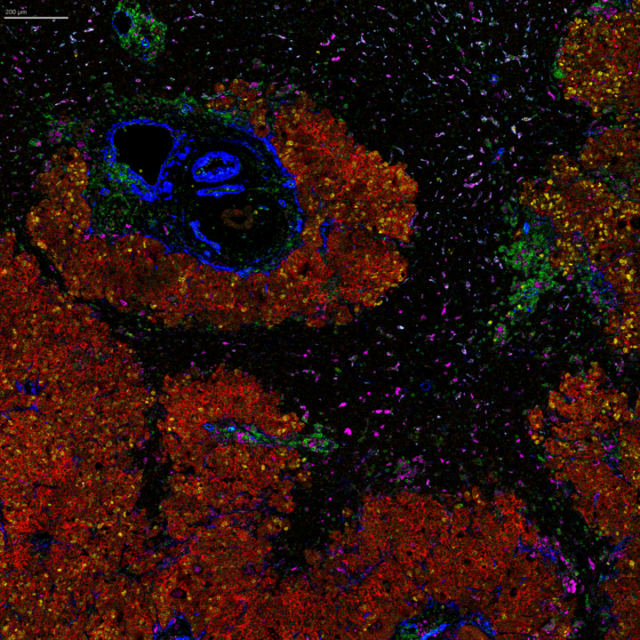

IMC platforms enable the comparison of spatial transcriptomic data with a choice of up to 45 spatial proteomic markers in the same section. This image shows six of 43 markers detected in the same scan.

Image of clear cell renal cell carcinoma tissue